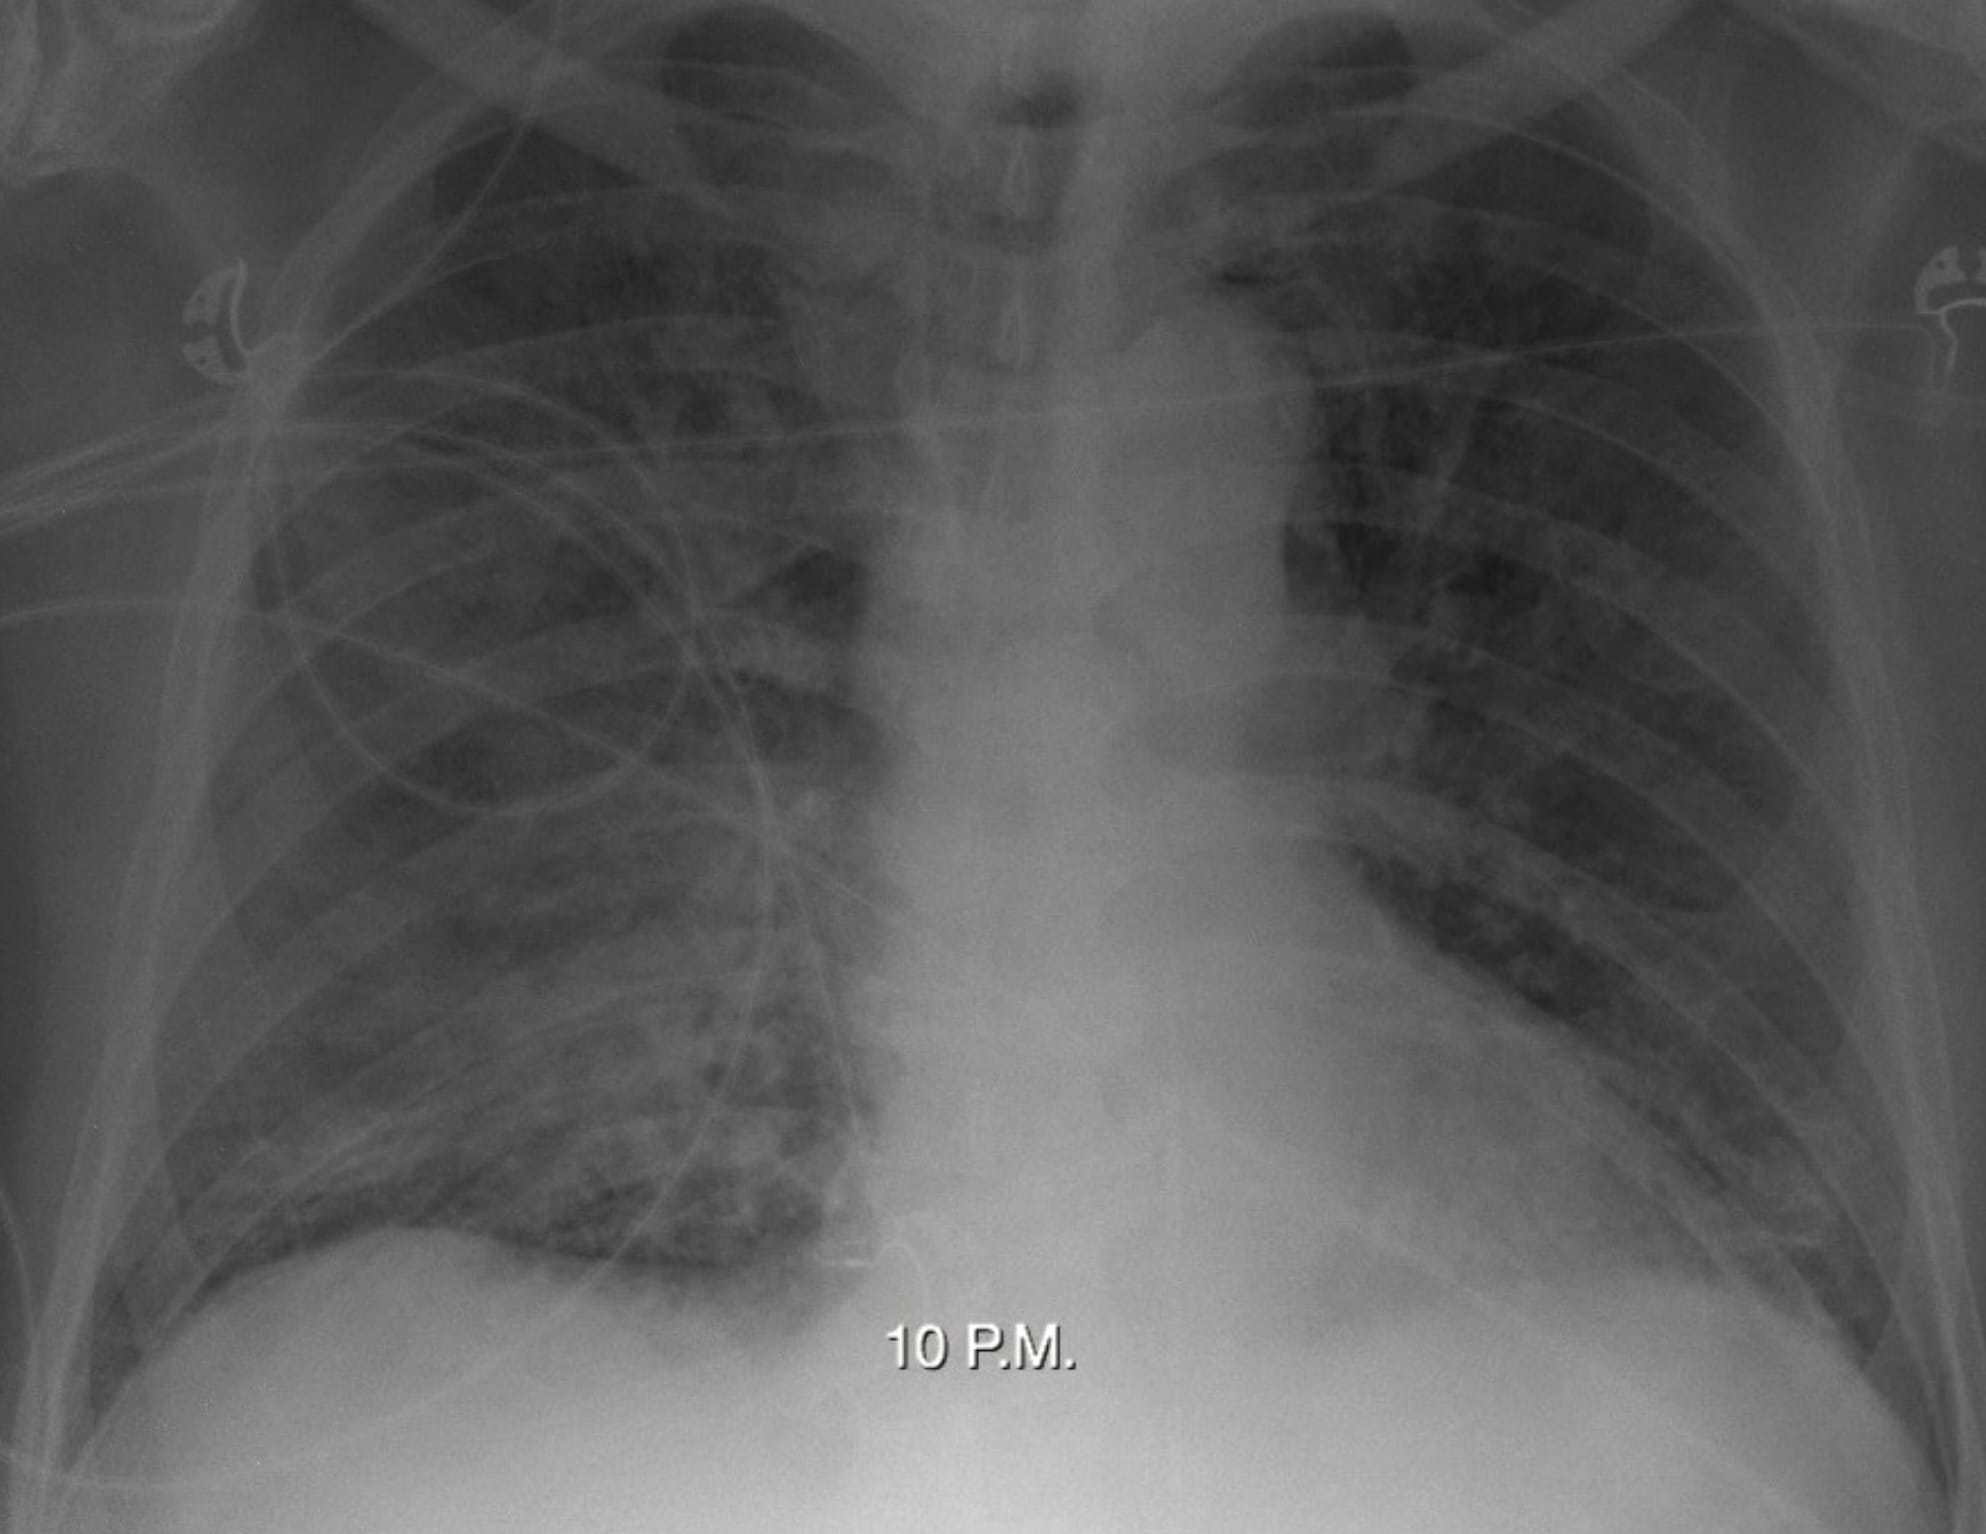

Here are four cases. Let’s try to determine, in each case, whether hydrostatic or acute lung injury edema is present, and the associated pathophysiology.

There is a history of mitral valve replacement.

A cardiac ultrasound report states: “Thrombus is present on the mechanical mitral valve prosthesis.

There is a marked pressure gradient (mean of 24mm Hg) implying thrombotic occlusion of the prosthesis.”

The “rules” appear to be broken. Case one represents acute lung edema from acute, severe left atrial hypertension. Yet, only minimal interstitial edema is present. Case two is high-altitude pulmonary edema; Case three is neurogenic lung edema. Case four is swimming-induced lung edema.

The explanation for these cases derives from the phenomenon of Stress Failure of Pulmonary Capillaries, a form of acute lung injury, involving the alveolar-capillary barrier. This was elucidated by John West – initially in the case of acute fatal lung edema in racehorses – and is nicely depicted in this figure from one of his articles.